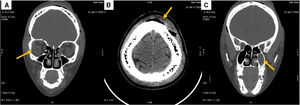

Evolución y diagnósticoAnte la sospecha de una infección de piel y partes blandas compleja, se complementó la terapia previa con ceftriaxona 2g intravenosa (iv) con cobertura adicional de vancomicina a una dosis de 15mg/kg iv cada 12 horas, previa dosis de carga de 25mg/kg. También se administró dexametasona a 4mg iv cada ocho horas como tratamiento coadyuvante para el edema palpebral grave. Debido a las limitaciones del hospital, que no dispone de tomografía computarizada (TC) de urgencia, se optó por realizar un drenaje transcutáneo mediante dos incisiones en el cuero cabelludo y a nivel palpebral bilateral, extrayéndose un litro de contenido purulento de colecciones subcutáneas. Las muestras enviadas al laboratorio de Microbiología revelaron el aislamiento de Staphylococcus aureus sensible a la meticilina. La TC realizada posteriormente confirmó la sospecha clínica, mostrando una celulitis orbitaria complicada con absceso orbitario y subgaleal frontal, con una posible afección subperióstica (fig. 2A y B), además de signos de sinusitis crónica en ambos senos frontales y en el seno maxilar izquierdo (fig. 2C).

El diagnóstico definitivo fue celulitis orbitaria abscesificada, extendida a territorio subgaleal como complicación de una probable sinusitis frontal y/o maxilar. La evolución clínica fue satisfactoria tras el drenaje transcutáneo realizado en el Servicio de Cirugía General y la administración de la antibioterapia mencionada durante siete días. Posteriormente, se ajustó el tratamiento tras los resultados del antibiograma a amoxicilina-clavulánico, completando un total de 21 días, con resolución total del cuadro.